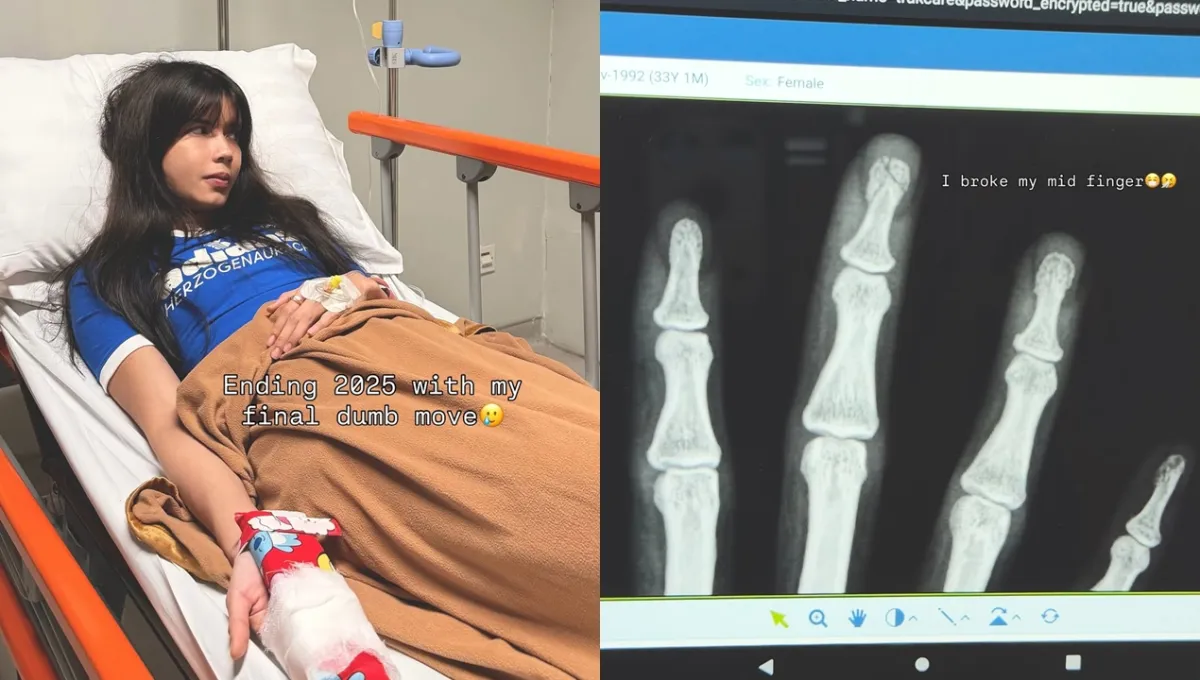

Kabar tersebut ia sampaikan langsung melalui unggahan terbaru di akun Instagram pribadinya. Dalam potret yang dibagikan, Sabrina terlihat terbaring di ranjang rumah sakit dengan kondisi yang tampak lemah.

Perempuan berusia 33 tahun itu menyertakan tulisan singkat pada fotonya. “Mengakhiri 2025 dengan kecerobohan,” tulisnya di dalam foto, Senin (22/12).

Lewat keterangan unggahan, Sabrina kemudian mengungkap apa yang sebenarnya terjadi. Ia menjelaskan bahwa dirinya mengalami kecelakaan ringan yang berujung pada retaknya tulang jari tengah di tangan kanan.

Kejadian tersebut, menurut Sabrina, berawal dari momen bercanda dengan seorang teman. Ia sempat mengirim meme bertema “melakukan satu kecerobohan sebelum pergantian tahun”, yang ternyata justru menjadi kenyataan tak lama setelahnya.

“Hati-hati kalau bercanda, aku serius. Aku mengirim satu meme ke seorang teman, bercanda tentang membuah kebodohan sebelum 2026 datang,” jelasnya dilansir brilio.net dari Kapanlagi, Selasa (23/12).

Mantan istri Deddy Corbuzier itu lalu menceritakan kejadian nahas yang menimpanya. “Beberapa jam setelahnya, aku meretakkan jari tengahku. Beneran retakin jari pas nutup pintu garasi besi. Bahkan aku bisa dengar suara pas tulangku retak, haha,” lanjutnya.